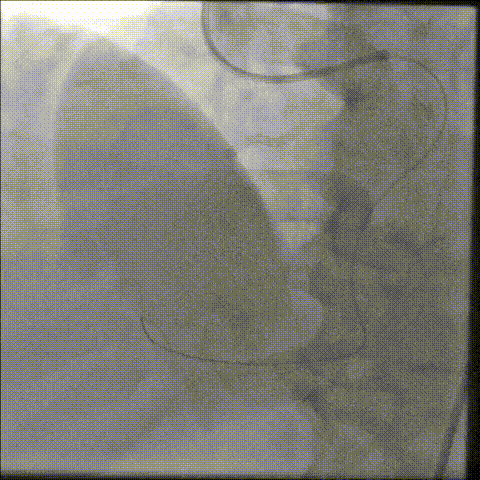

انژیوگرافی یک روش تصویربرداری پیشرفته است که به ما امکان میدهد وضعیت رگهای خونی قلب شما را با دقت بررسی کنیم و هرگونه انسداد یا تنگی را شناسایی کنیم. در صورت نیاز، با استفاده از انژیوپلاستی، که شامل باز کردن رگهای مسدود شده با استفاده از بالون و استنت میباشد، جریان خون به قلب شما را بهبود میبخشیم. با تکیه بر تجربه و تخصص من، اطمینان حاصل کنید که قلب شما در بهترین دستان قرار دارد. برای مشاوره و اطلاعات بیشتر، با من تماس بگیرید. تعویض دریچه قلب یک روش جراحی پیشرفته است که برای درمان دریچههای آسیبدیده یا نارسای قلب به کار میرود. این عمل به بهبود عملکرد قلب و افزایش کیفیت زندگی بیماران کمک میکند. دریچههای قلب نقش حیاتی در تنظیم جریان خون در داخل قلب و به سایر قسمتهای بدن دارند؛ بنابراین، هرگونه نقص یا آسیب در این دریچهها میتواند منجر به مشکلات جدی سلامتی شود.